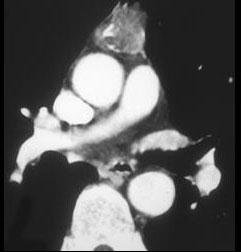

问题 男,45岁,胸骨后隐痛伴四肢无力3月余,请结合影像学检查,选出最可能的诊断 ( )

选项 A、淋巴瘤 B、间皮囊肿 C、纵隔畸胎瘤 D、胸腺瘤 E、胸内甲状腺肿

答案 D